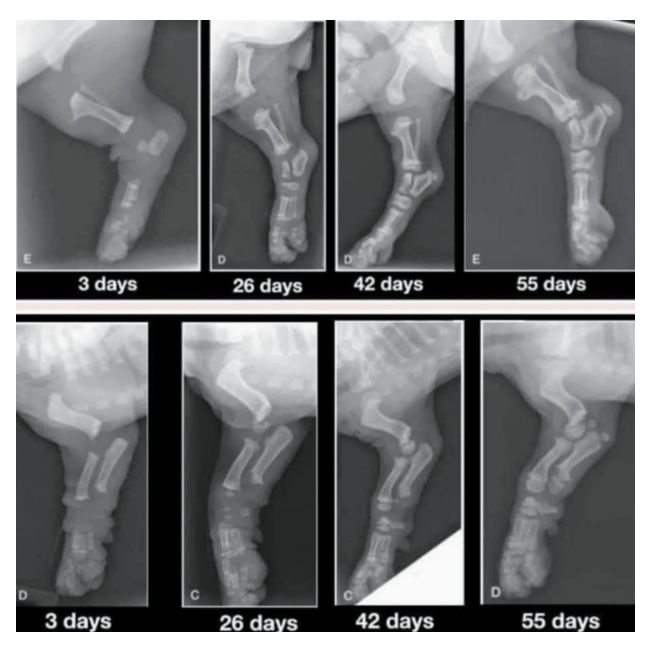

The first concept to understand when it comes to puppy exercise is “growth plates.” Growth plates are soft areas that sit at the ends of the long bones in puppies and young dogs. They contain rapidly dividing cells that allow bones to become longer until the end of puberty.

Growth plates gradually thin as hormonal changes approaching puberty signal the growth plates to close. In puppies, this closure is normally completed by approximately 18 months old.

Until the growth plates close, they’re soft and vulnerable to injury.

After sexual maturity, the growth plates calcify and the rapid cell division ends. The growth plate becomes a stable, inactive part of the bone, now known as an epiphyseal line.In addition to having soft growth plates at the end of long bones, a puppy’s bones in general are “softer.” Dogs, like people, don’t reach their maximum bone density until after puberty.

When you get your puppy, PLEASE keep this image in mind. Their bones do not even touch yet. They plod around so cutely with big floppy paws because their joints are entirely made up of muscle, tendons and ligament with a skin covering. Nothing is fitting together tightly or has a true socket yet.

Early spay/neuter delays the closure of growth plates in the bones, due to removal of normal growth/sex hormones. When the growth plates stay open beyond the point they should normally close, the growth continues in the long bones, leading to a taller, more narrow and leggy dog. This change in conformation increases the risk of several orthopedic problems, including hip dysplasia, elbow dysplasia, luxating patellas, and torn cruciate ligaments.